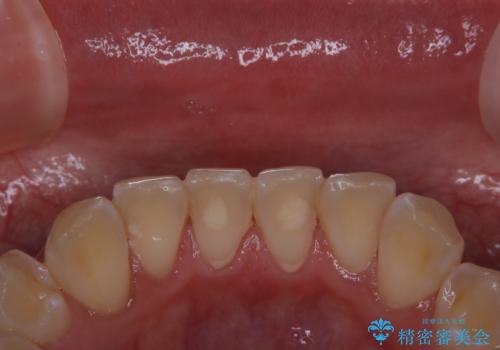

PMTCでは、プラークや歯石、着色などを徹底的に除去します。

まずは、ご自身本来の歯の状態にしてからホワイトニングを行うか検討してもらうことをおすすめします。

よりお口の中を健康な状態にしてからホワイトニング治療のを受けることで効果を安全で確実に得ることができます。